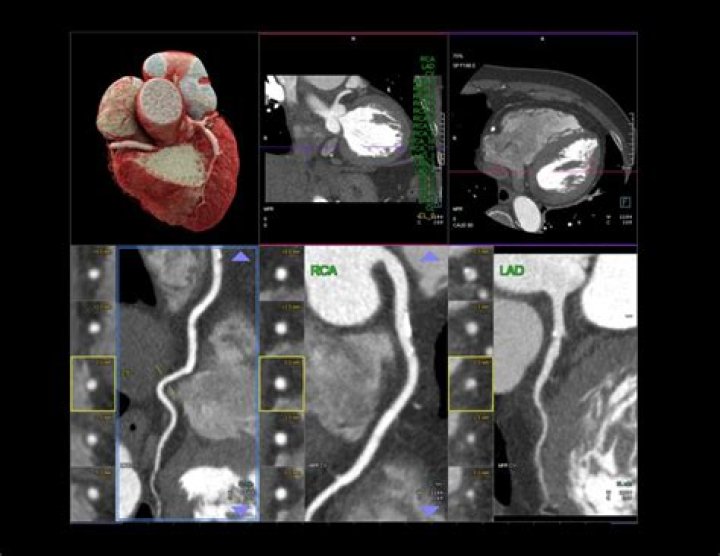

A CT coronary angiogram can reveal plaque buildup and identify blockages in the arteries, which can lead to a heart attack. Prior to the test, a contrast dye is injected into the arm to make the arteries more visible. The test typically takes 30 minutes to complete.

There are several types of CT scans used in the diagnosis of heart disease, including: Calcium-score screening heart scan. Coronary CT angiography (CTA) Total body CT scan.

What is the difference between a CT scan and a CT angiogram?

Computed tomography (CT) scan is a type of x-ray that uses a computer to take cross-sectional images of your body. Computed tomography angiography (CTA) combines a CT scan with a special dye or contrast material to produce pictures of blood vessels and tissues in a section of your body.